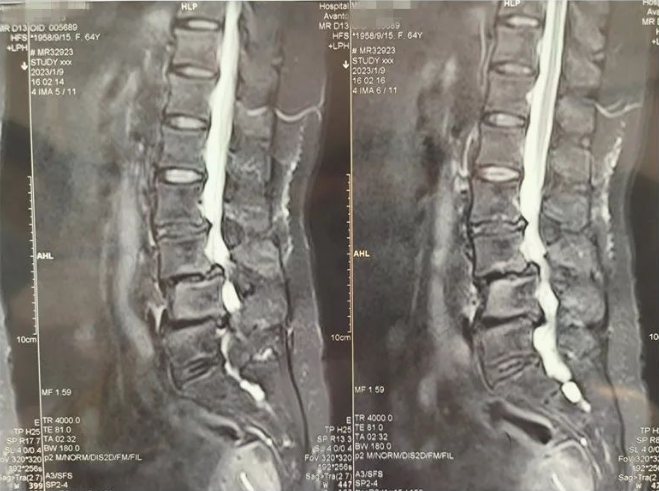

患者术前影像资料

通过影像学资料结合查体,王某诊断为"腰椎滑脱 腰椎管狭窄"。影像资料提示,王某腰L4椎体滑脱,腰L4-L5间隙变窄,椎间盘突出,椎管狭窄,神经根受压。